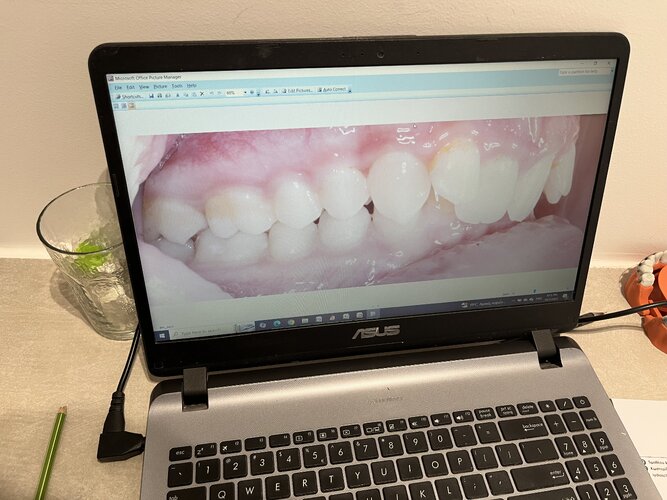

Important to note that my maxilla wasn’t downward grown until braces and headgear I am still 16 and upward thumb pressure is is not really doing anything much (I also had to fix my skeletal issue with my palate because my ortho only did tooth expansion instead of marpe/sarpe (aka breathing issues)